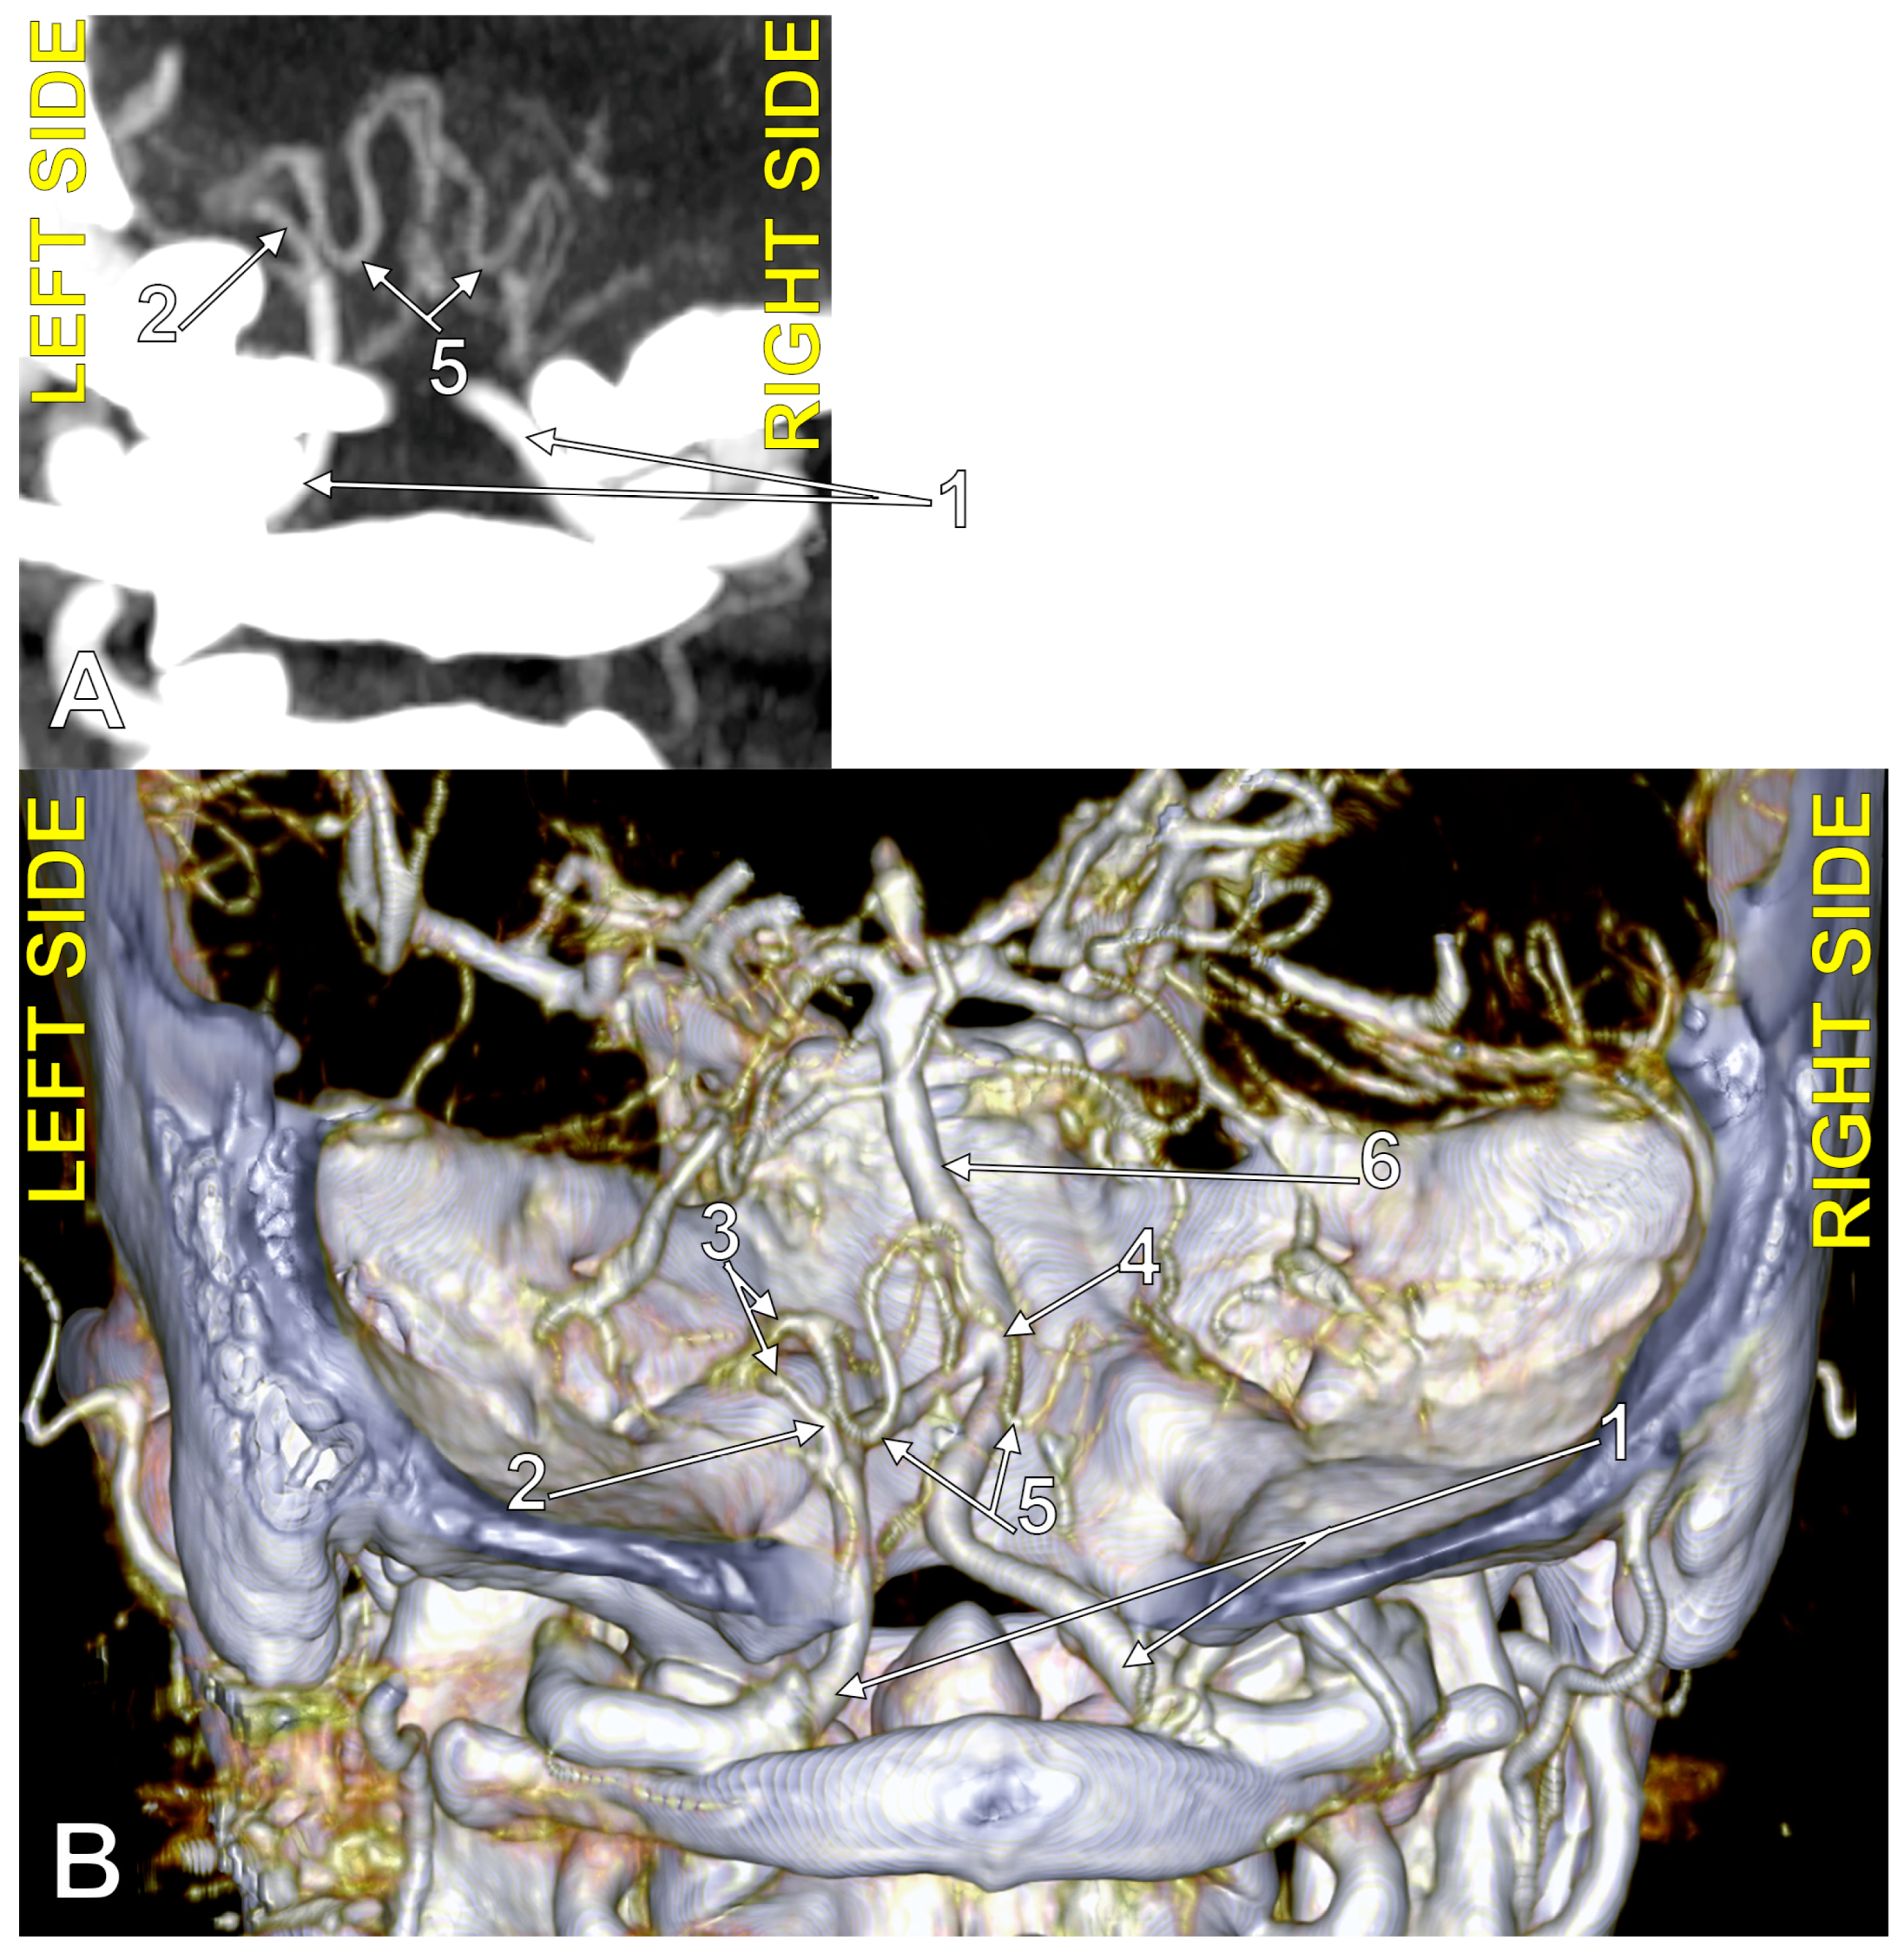

4.1. Typical PICA

4.3. Extradural Origin of the PICA

4.4. Transdural Origin of the PICA

4.5. The PICA and the Marginal Sinus

4.6. The PICA and the Dural Ring of the VA

4.8. The Caudal Loop of the PICA